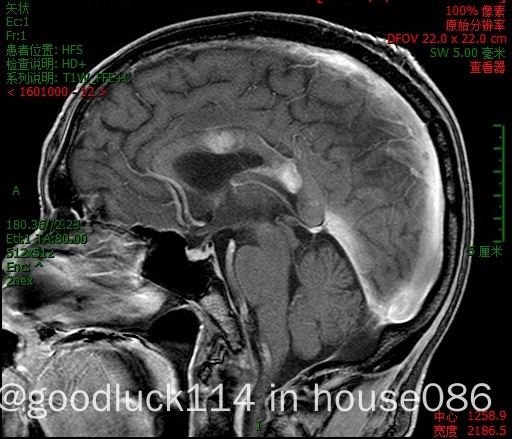

高龄取不了病理,医院做不了pet-ct,做了头颅ct和mri,发现颅内占位性病变,怀疑原发或转移,但胸部ct腹部ct和肿瘤标志物都没有明显异常,也没有除神经系统外其他系统的症状,mri增强结果不像是胶质瘤,高度怀疑是原发性中枢淋巴瘤。